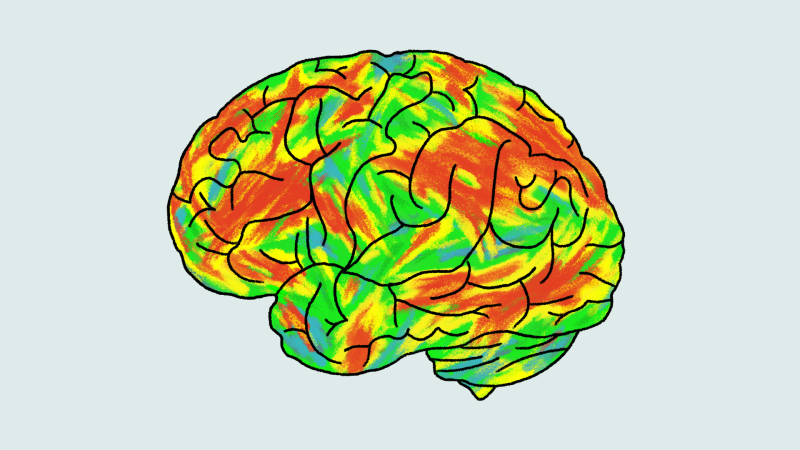

The matchup: Two doses of psilocybin, the active ingredient in “magic mushrooms,” against a six-week course of the popular antidepressant escitalopram, often sold as Lexapro or Cipralex. Escitalopram is one